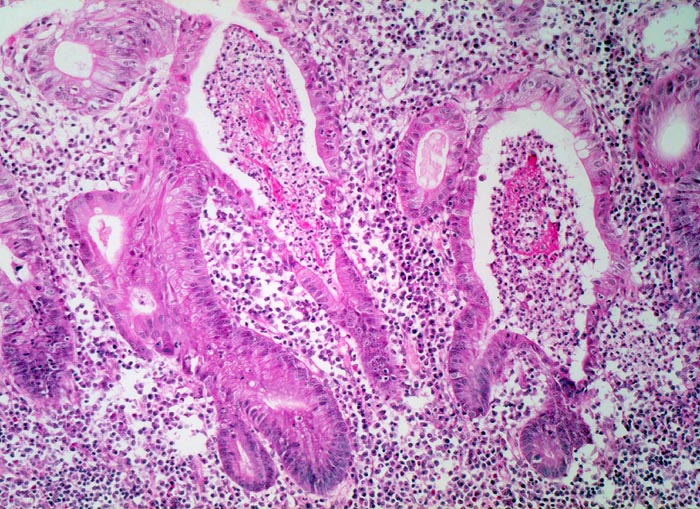

Colitis ulcerosa

Gestörte Kryptenarchitektur mit verzweigten Krypten. Verdichtetes Entzündungsinfiltrat in der Lamina propria. Dilatierte Krypten gefüllt mit Fibrin und neutrophilen Granulozyten (=Kryptenabszess). Praktisch vollständiger Verlust von schleimbildenden Becherzellen und Basophilie (bläuliche Farbe) des Epithels.

Becherzellverlust und Basophilie des Epithels stellen unspezifische regeneratorische Veränderungen im Rahmen der Entzündung dar. Der Becherzellverlust ist bei Colitis ulcerosa oft sehr stark ausgeprägt verglichen mit anderen entzündlichen Darmerkrankungen.